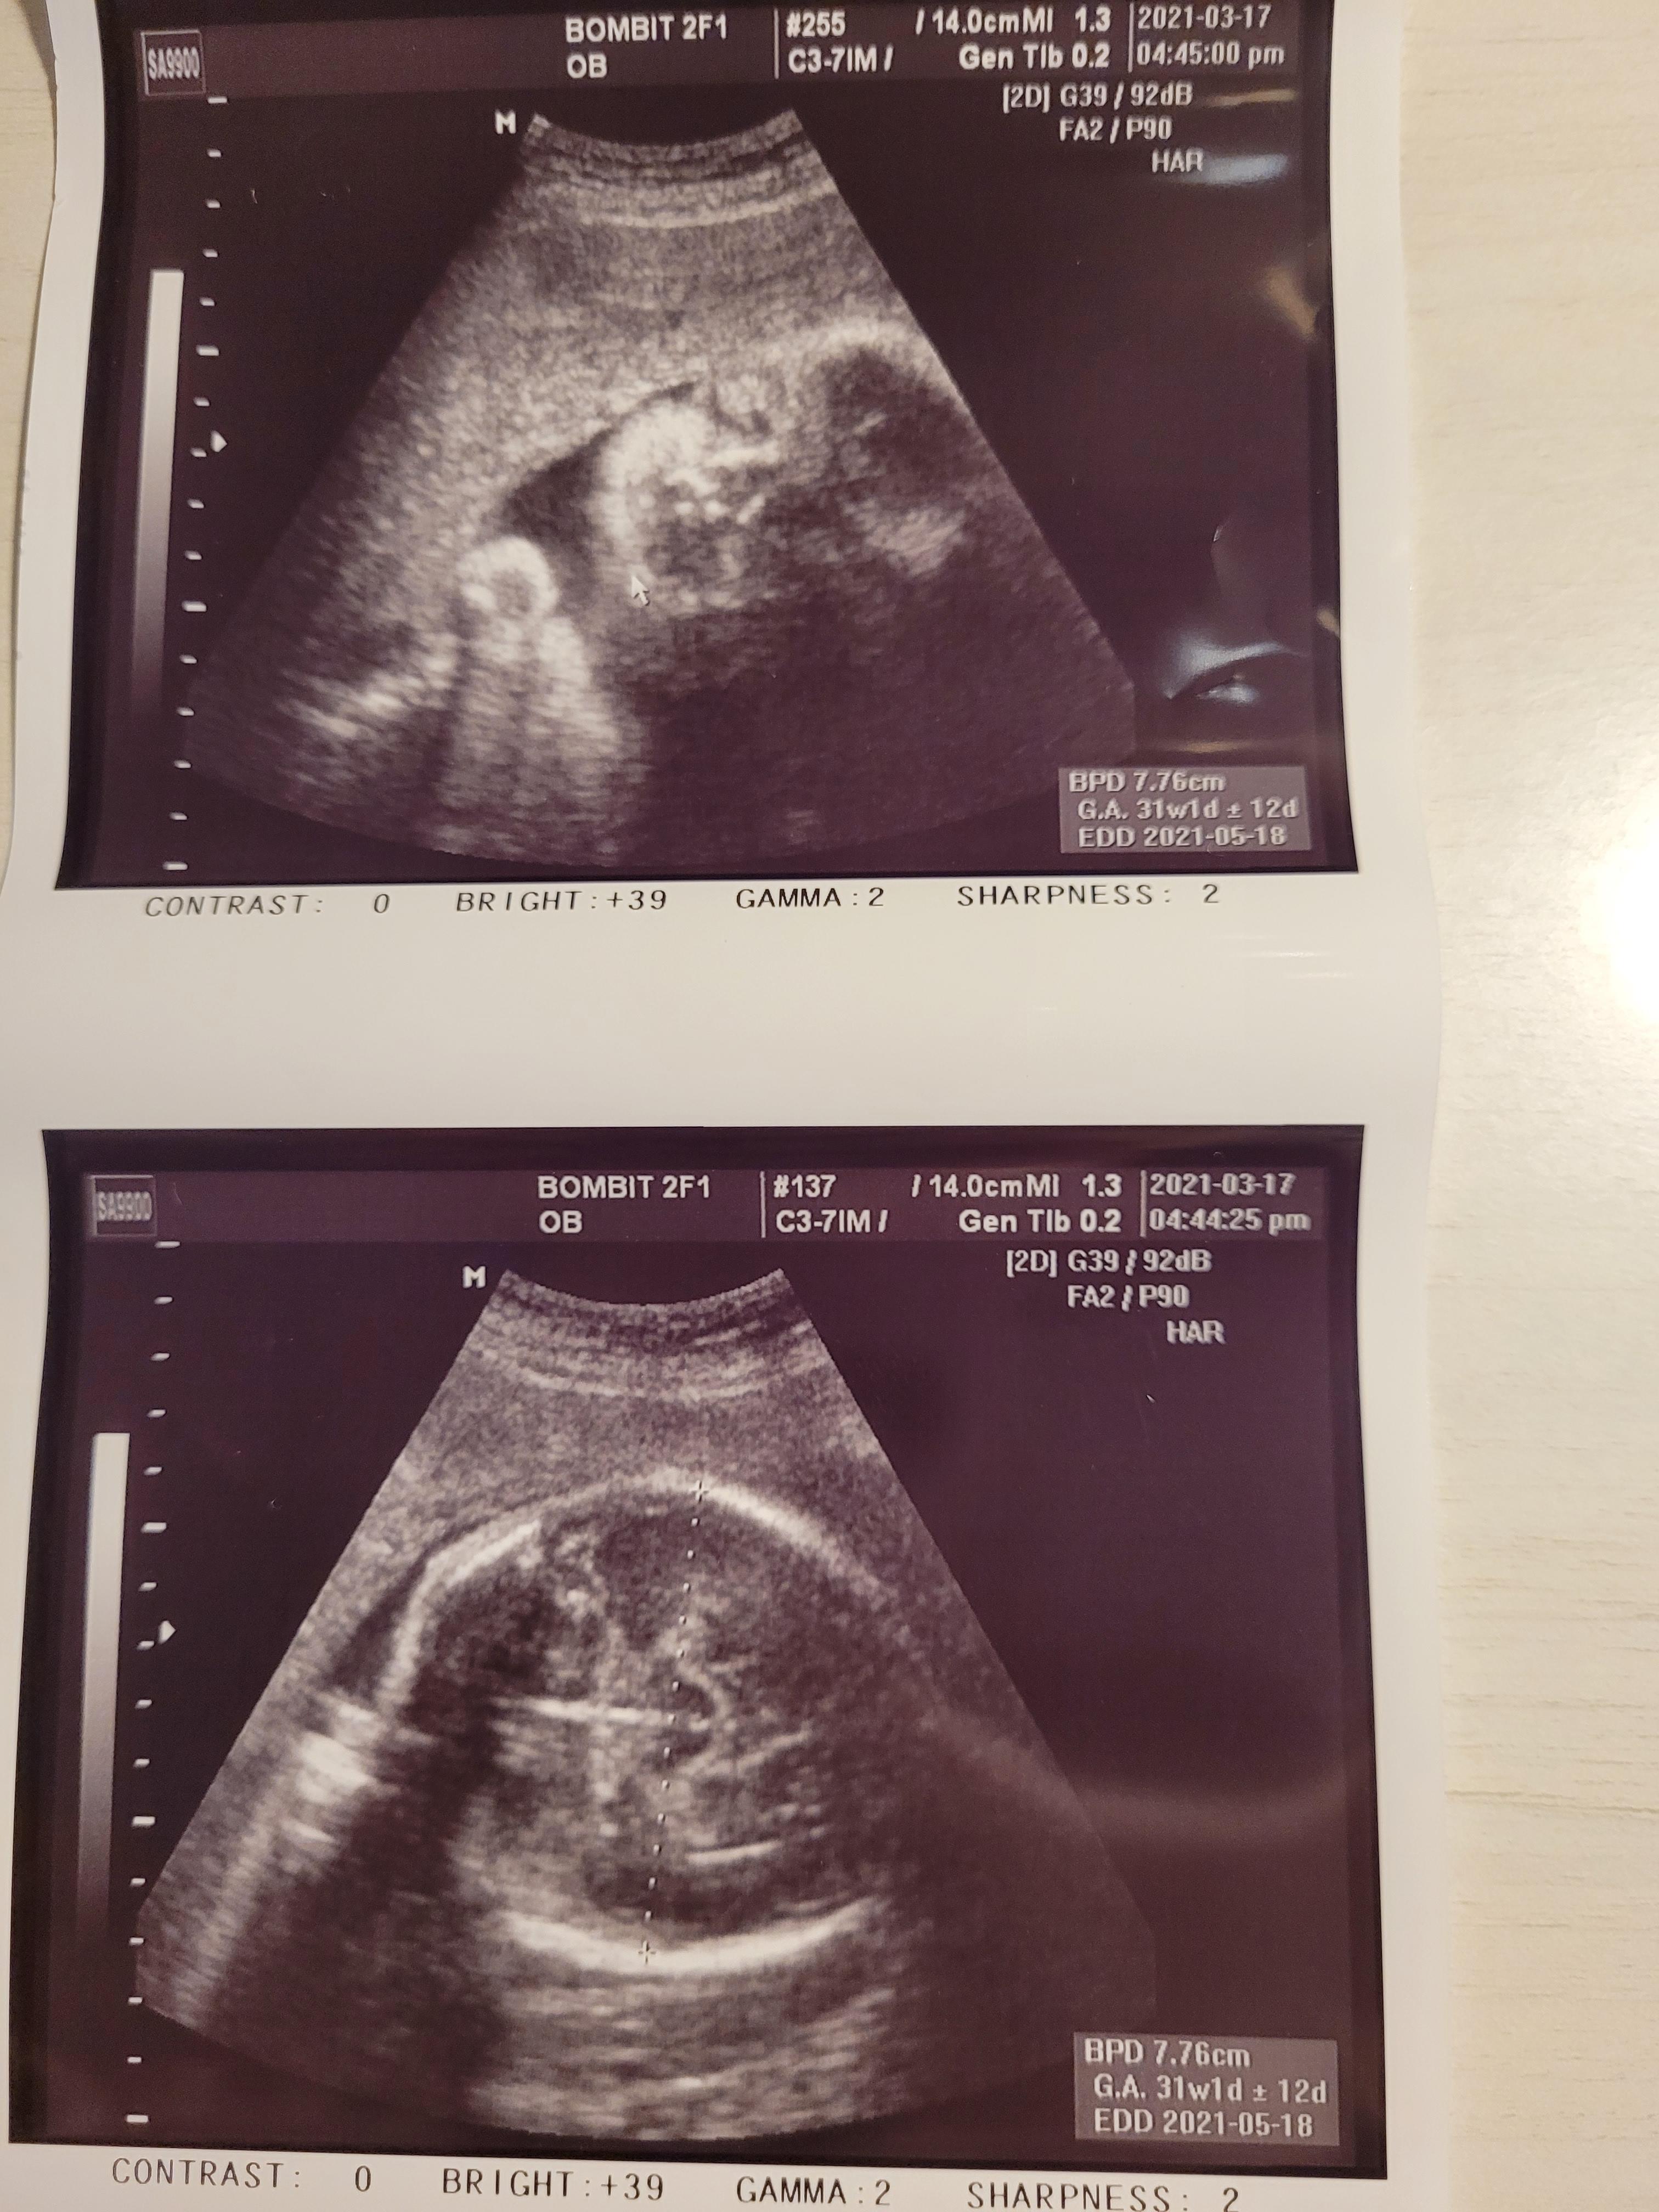

머리크기는 이미 31주가 넘어간 우리 행복이..

잘 크고있어서 다행인데, 너무 크면 나중에 출산할때 힘들것같더라고요.

심장도 잘뛰고, 머리부터 발끝까지 다 잘 있어서 얼마나 다행인지 몰라요.

양수도 넉넉하고, 아기도 잘 크고있어서 한시름 놓았어요.

경부길이도 3.57cm로 짧은편은 아니어서 위험한 상황은 아니네요.